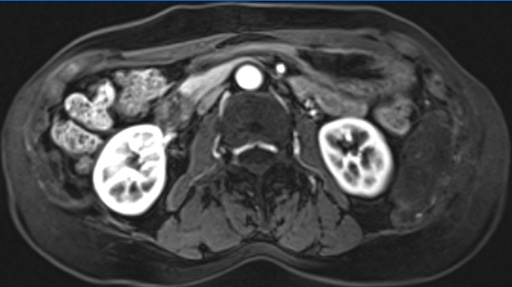

図1 腹部造影CT

図1 腹部造影CT

(右腎上極レベル) 図2 腹部造影CT

図2 腹部造影CT